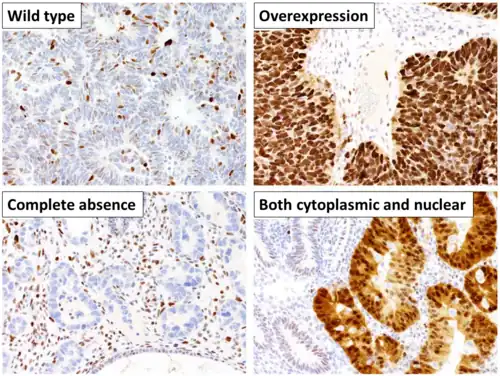

Diagnostic and prognostic significance

This image shows different patterns of p53 expression in endometrial cancers on chromogenic immunohistochemistry, whereof all except wild-type are variably termed abnormal/aberrant/mutation-type and are strongly predictive of an underlying TP53 mutation:[92]